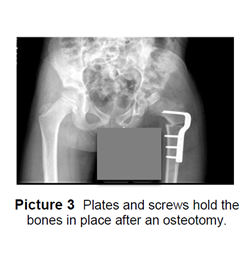

- An osteotomy, (cutting the bone and repositioning it more correctly) is done when the bone has redeveloped incorrectly. Plates and screws are used to hold the correct position of the bone until it has healed (Picture 3). Cast, crutches or a walker and an abduction pillow may be used after surgery to help keep the hip in the proper position and promote healing.